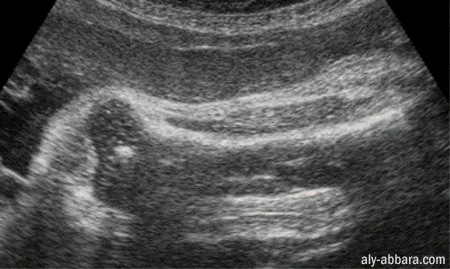

Le fémur ftal (l'os de la cuisse)

: les parties ossifiées

de la diaphyse et l'extrémité inférieur del'os

à 35 semaines d'aménorrhée

Coupe logitudinale passant par la diaphyse et l'extrémité

inférieure de l'os

On peut distinguer sur cette image

échographique les parties ossifiées du fémur à

ce terme de

grossesse, à savoir, la diaphyse et le point d'ossification de Beclard

au niveau de l'épiphyse inférieure.

Voir l'extrémité

supérieure du fémur